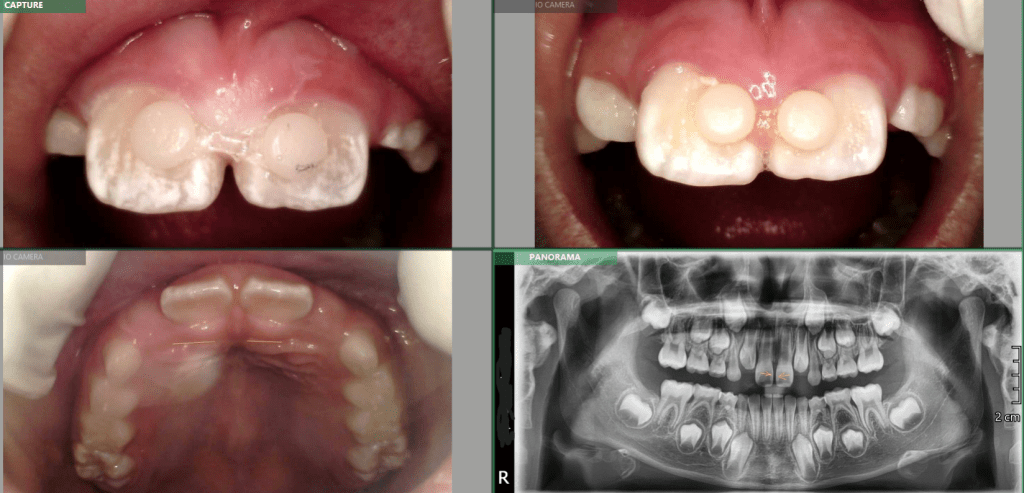

Case Study – Chloe.W – Early Intervention Orthodontics – Severe Overjet

Adaptive Orthodontics Pre-Op Analysis – 2020-11-25 Age : 9 Class 2 div I and div IIMixed DentitionLower lip entrapment NORMALLY LOWER LIP ENTRAPPED BEHIND UPPER ANTERIOR NORMALLY LOWER LIP ENTRAPPED BEHIND UPPER ANTERIOR PROCLINE (OVERJET) UPPER ANTERIORDIASTEMA (SPACING) – TONGUE THRUSTLOWER LIP ENTRAPMENTNARROW (GOTHIC) ARCHDEEP BITE – SOFT TISSUE TRAUMA STAGE 1 RETRACT UPPER ANTERIORS… Read.